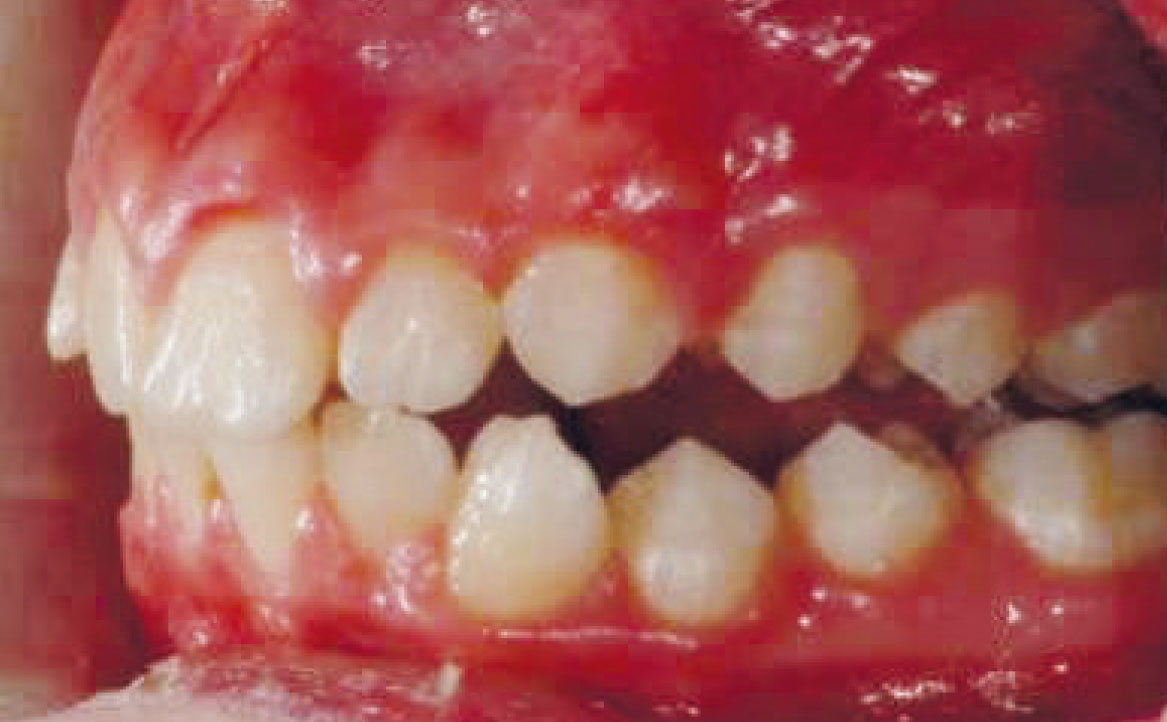

Paziente di genere femminile di otto anni affetta da una malocclusione di classe II sia dentale che scheletrica, associata a una condizione di retrusione mandibolare e contrazione dell’arcata superiore. Non si rilevano problemi dentali significativi.

Viene eseguita la consueta raccolta dei records: fotografie intra ed extra orali, modelli e indagini radiografiche di primo livello (OPT e teleradiografia latero-laterale) (fig. 2-11).

La buona collaborazione della paziente ha consentito di ottenere un buon avanzamento mandibolare, la correzione delle classi canina e molare (ben evidenti nelle fotografie intra orali mostrate in fig. 15 e 17). Il morso aperto residuo verrà corretto mediante immediato inizio della terapia ortodontica fissa al fine di abbreviare la durata complessiva del trattamento.